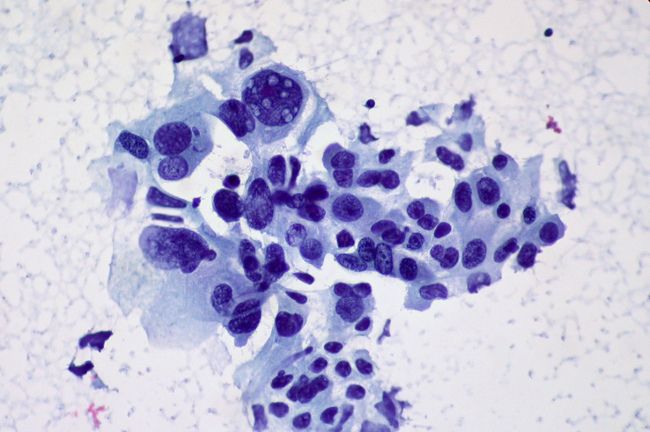

Сегодня компания использует уже имеющиеся базы данных, которые были созданы в китайских больницах после вспышки атипичной пневмонии в 2003 году. Infervision использует данные изображений, хранящиеся в цифровых медицинских записях, и связывает их с данными технологии компании собираемыми в 20 больницах по всему Китаю.

Infervision также работает с компанией GE Healthcare, Cisco и Nvidia, чтобы развивать и совершенствовать свои технологии. Компания переработала около 100 000 изображений компьютерной томографии и 100 000 рентгеновских снимков в прошлом году.